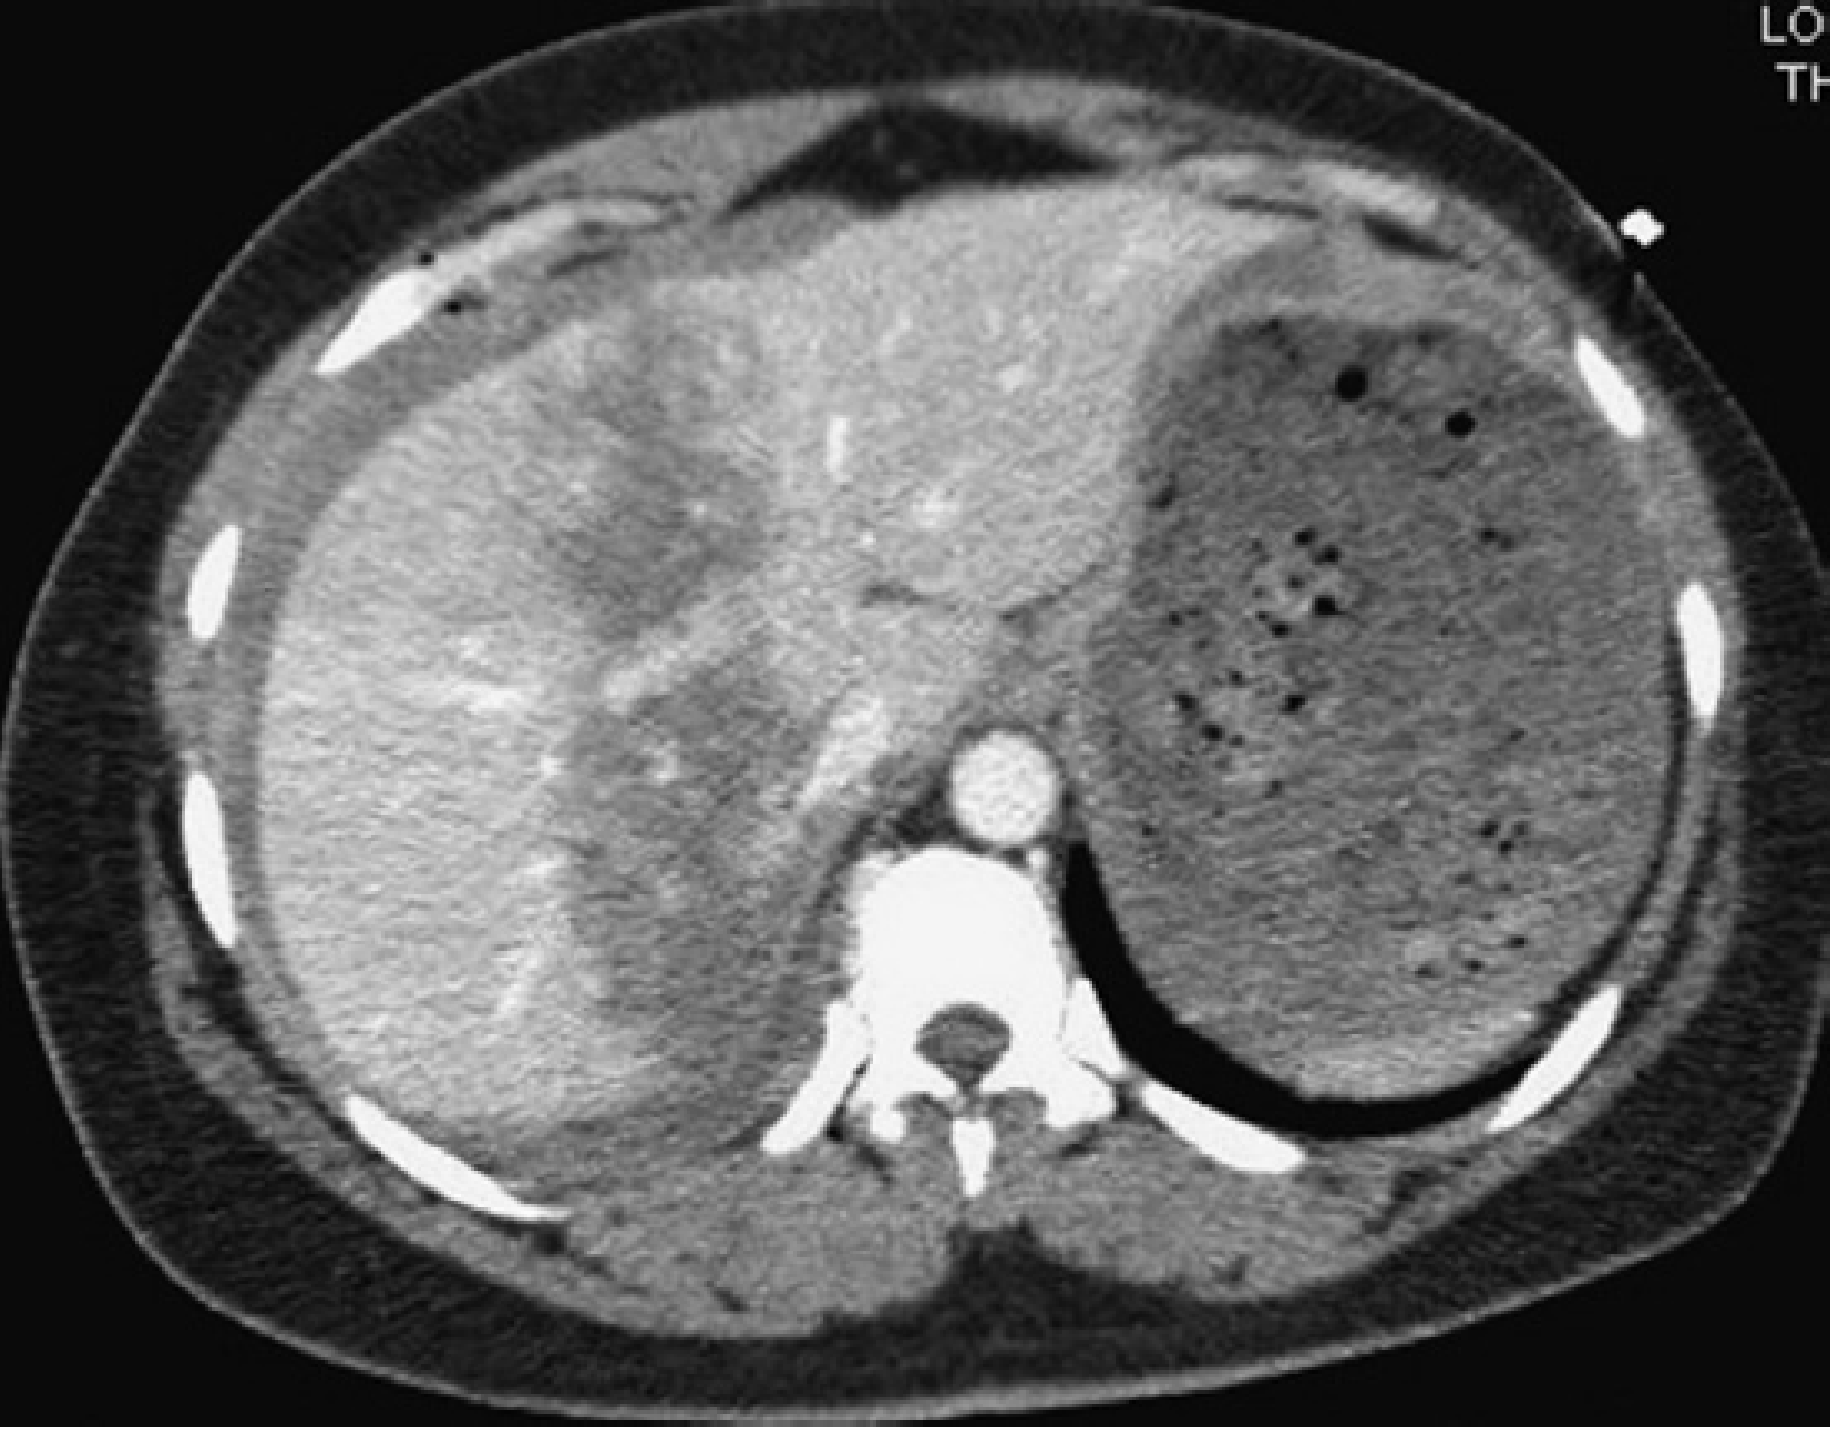

CT images of liver injury:

CT of liver injury grades

CT liver injury

CT images of liver injury — Current Surgical Therapy 14e, p. 1342

Figure — Gunshot injury to the liver successfully managed nonoperatively:

Gunshot liver NOM

Mulholland and Greenfield's Surgery, p. 1280